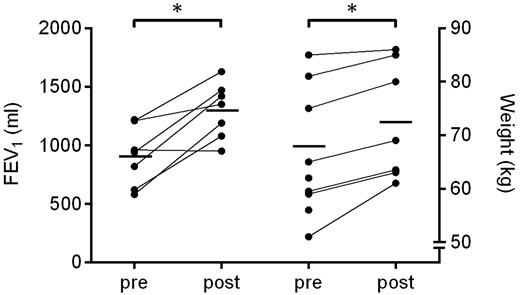

- 在12個(gè)月的隨訪中,? 與基線相比,F(xiàn)EV1增加了390 ml±240ml(P=0.03)。

- 所有患者的體重均顯著增加,平均增加4.6公斤(范圍1–10公斤;P=0.016)(圖 2)。